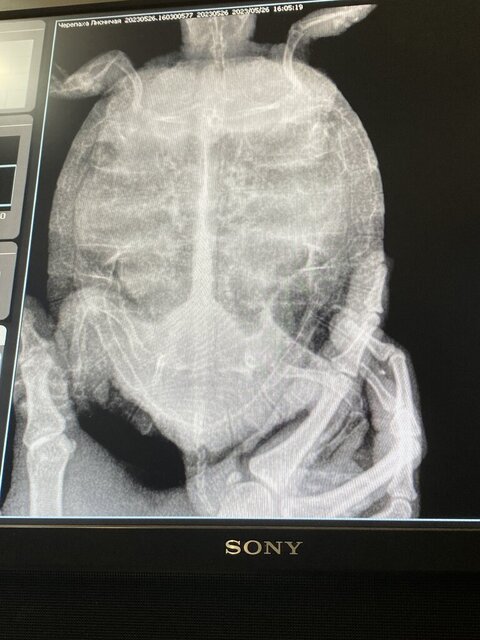

Проблема болезни: стала вялой, сидит уже месяц на островке в воду сама не идёт, аппетит не пропадал до недавнего времени , если опускала  в воду то правый бок в низу, а левый поднят вверх, по симптомам определила пневмонию. 27 мая отнесла к ветеринару, сделали рентген и подтвердили пневмонию, 7 дней прокололи байтрил 0,1 мл., лучше не стало, 5 июня обратила внимание что начали заплывать глаза с нижней части глаза, обратилась снова к ветеринару назначили марфлоксин в дозировке 0,05 ( сделала 2 укола, 5 и 6 июня ). 7 июня обратились снова к ветеринару  назначили катозал 0,1 мл. и антибиотик амоксицилин 0,05 мл. Катозал укололи , а антибиотик ещё нет ( боюсь уже колоть ), назначили колоть катозал и асоксицилин каждый день с интервалом в 15 мин.Состояние черепахи ухудшается с каждым днём, глаза почти не открываются, сегодня при дыхании начала открывать рот . Ещё я начала ей делать ванночки с ромашки и грудной сбор 2-3 раза в день , делаю уже 3 дня ( температура воды в ванночке 35-40 градусов ).И ещё у неё правее от хвоста какая-то шишка. Добавлю снимок, сделан был 26 мая.

хоть эта клиника и находится у нас в зеленом списке, но здесь явно ошибка в диагнозе и назначениях. По такой проекции невозможно оценить состояние лёгких.